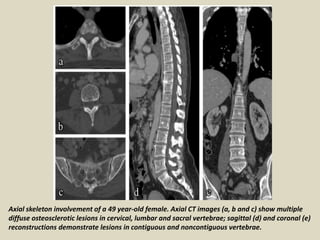

Axial skeleton involvement of a 49 year-old female. Axial CT images (a, b and c) show multiple

diffuse osteosclerotic lesions in cervical, lumbar and sacral vertebrae; sagittal (d) and coronal (e)

reconstructions demonstrate lesions in contiguous and noncontiguous vertebrae.